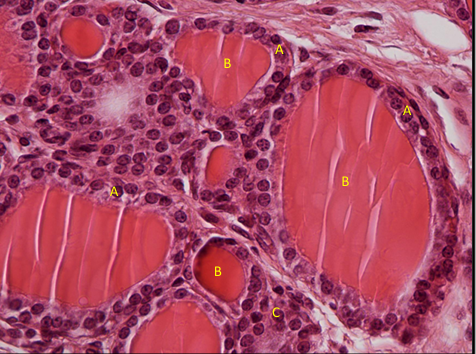

komórki pęcherzykowe = nabłonek jednowarstwowy sześcienny

koloid

komórki C

tarczyca (f. gruczołowa endokrynna nabłonka) nr 408